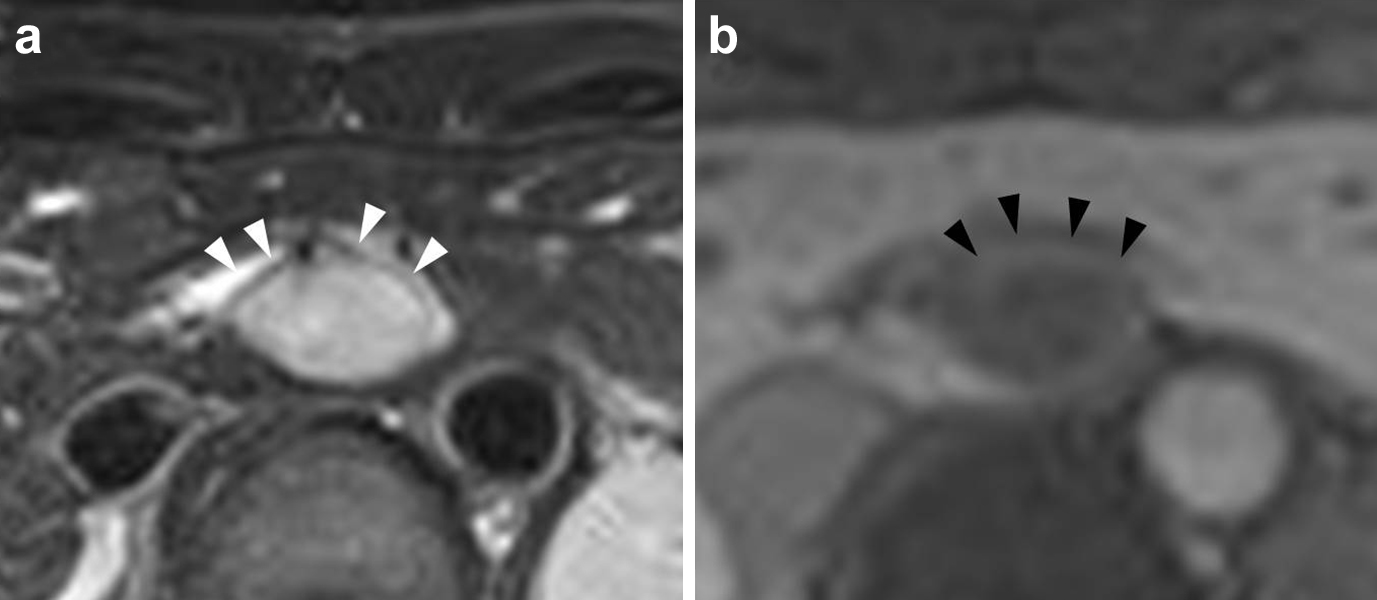

腹部造影MRI所見(初診時):肝尾状葉腹側に境界明瞭な腫瘤を認めた.腫瘤はT1強調画像で低信号,T2強調画像で低信号な被膜を有する高信号であった.また,dynamic studyで腫瘤辺縁部が被膜状に淡く造影された(Fig. 3).

On abdominal contrast MRI, the tumor had a hyperintense signal surrounded by low intensity coating on T2-weighted images (a) and the edge of the tumor was enhanced in a dynamic study (b).